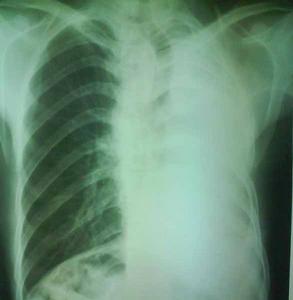

上腔靜脈受壓綜合徵胸腔積液

診斷:出現典型的體徵和症狀時,上腔靜脈受壓綜合徵是很易診斷的。當上腔靜脈受壓綜合徵表現不典型時,應藉助於血管造影、核素靜脈造影確定阻塞部位及病因。CT 增強掃描是常選用的方法,MRI 也可選用,可顯示腫塊、血栓和側支循環。X 線檢查最常用,Parish 等報導上腔靜脈受壓綜合徵80 例的胸部X 線表現:上縱隔增寬占64%,胸腔積液占26%,右肺門腫塊占12%,肺炎性浸潤占7%,氣管旁淋巴結占5%,縱隔腫物占3%,胸部X 線表現正常占16%。上腔靜脈受壓綜合徵常常發生在腫瘤進展期過程中,大多數情況下,病因診斷比較容易,但少部分病人病因診斷是比較困難的。在臨床工作中,首先應作出病因學診斷,在病因診斷困難的情況下,也應有充分的臨床證據,然後再處理,否則,不宜進行抗腫瘤治療。

其他輔助檢查:X 線檢查最常見:縱隔增寬,右肺門腫塊,少數肺炎性浸潤影。